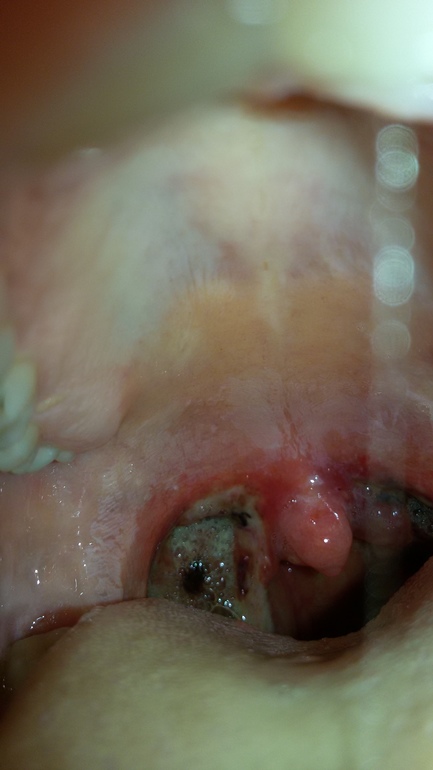

Кто хочет глянуть на мой страшный рот идите под кат ))) мне больно и грустно и из развлечений у меня телефон - вот и фоткаю что там у меня ))) разговаривать низзя пока.... молчу и мычу )))